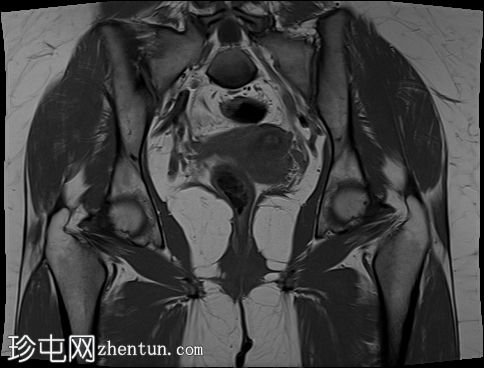

轴位

斜位T2加权像

子宫外底轮廓清晰,肌层较厚,将子宫内膜腔分隔成两个腔,纤维层较薄,向下延伸至宫颈外口。子宫内膜厚度正常,两个子宫腔交界区清晰,未见明显的实性局灶性病变。

本病例展示了典型的纵隔子宫影像学表现:增厚的肌层隔膜将子宫内膜腔分隔成两个腔,并有一层薄的纤维隔膜延伸至子宫颈外口水平,符合完全纵隔子宫的特征。

在MRI图像上,纵隔子宫通常大小正常,但每个子宫腔的形态均小于正常子宫腔。

隔膜可能由纤维组织(T2信号低)、肌层组织(中等信号)或两者共同构成,如本病例所示。